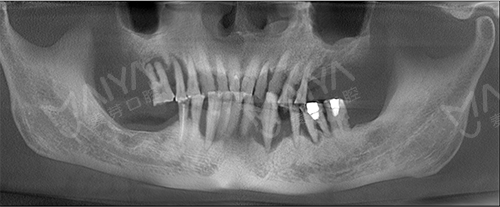

李大爷到院拍完CT和口腔全景片,了解到情况后,麦芽口腔的种植技术院长指出:由于长期对口腔疏于护理,李老的牙周情况非常差,余牙松动,且牙槽骨萎缩、吸收,现存骨量无法进行传统的种植牙术式。

麦芽的院长指出, All-ON-4种植牙技术打破传统种植技术瓶颈,可以破解牙槽骨萎缩、骨量不足等种植难题,而且手术过程无需植骨,让老年缺牙群体也能实现快速种牙。麦芽口腔院长针对李大爷的情况,对ALL-ON-4种植技术进行升级和改造,为其量身定制了“ALL-ON-5”种植方案。